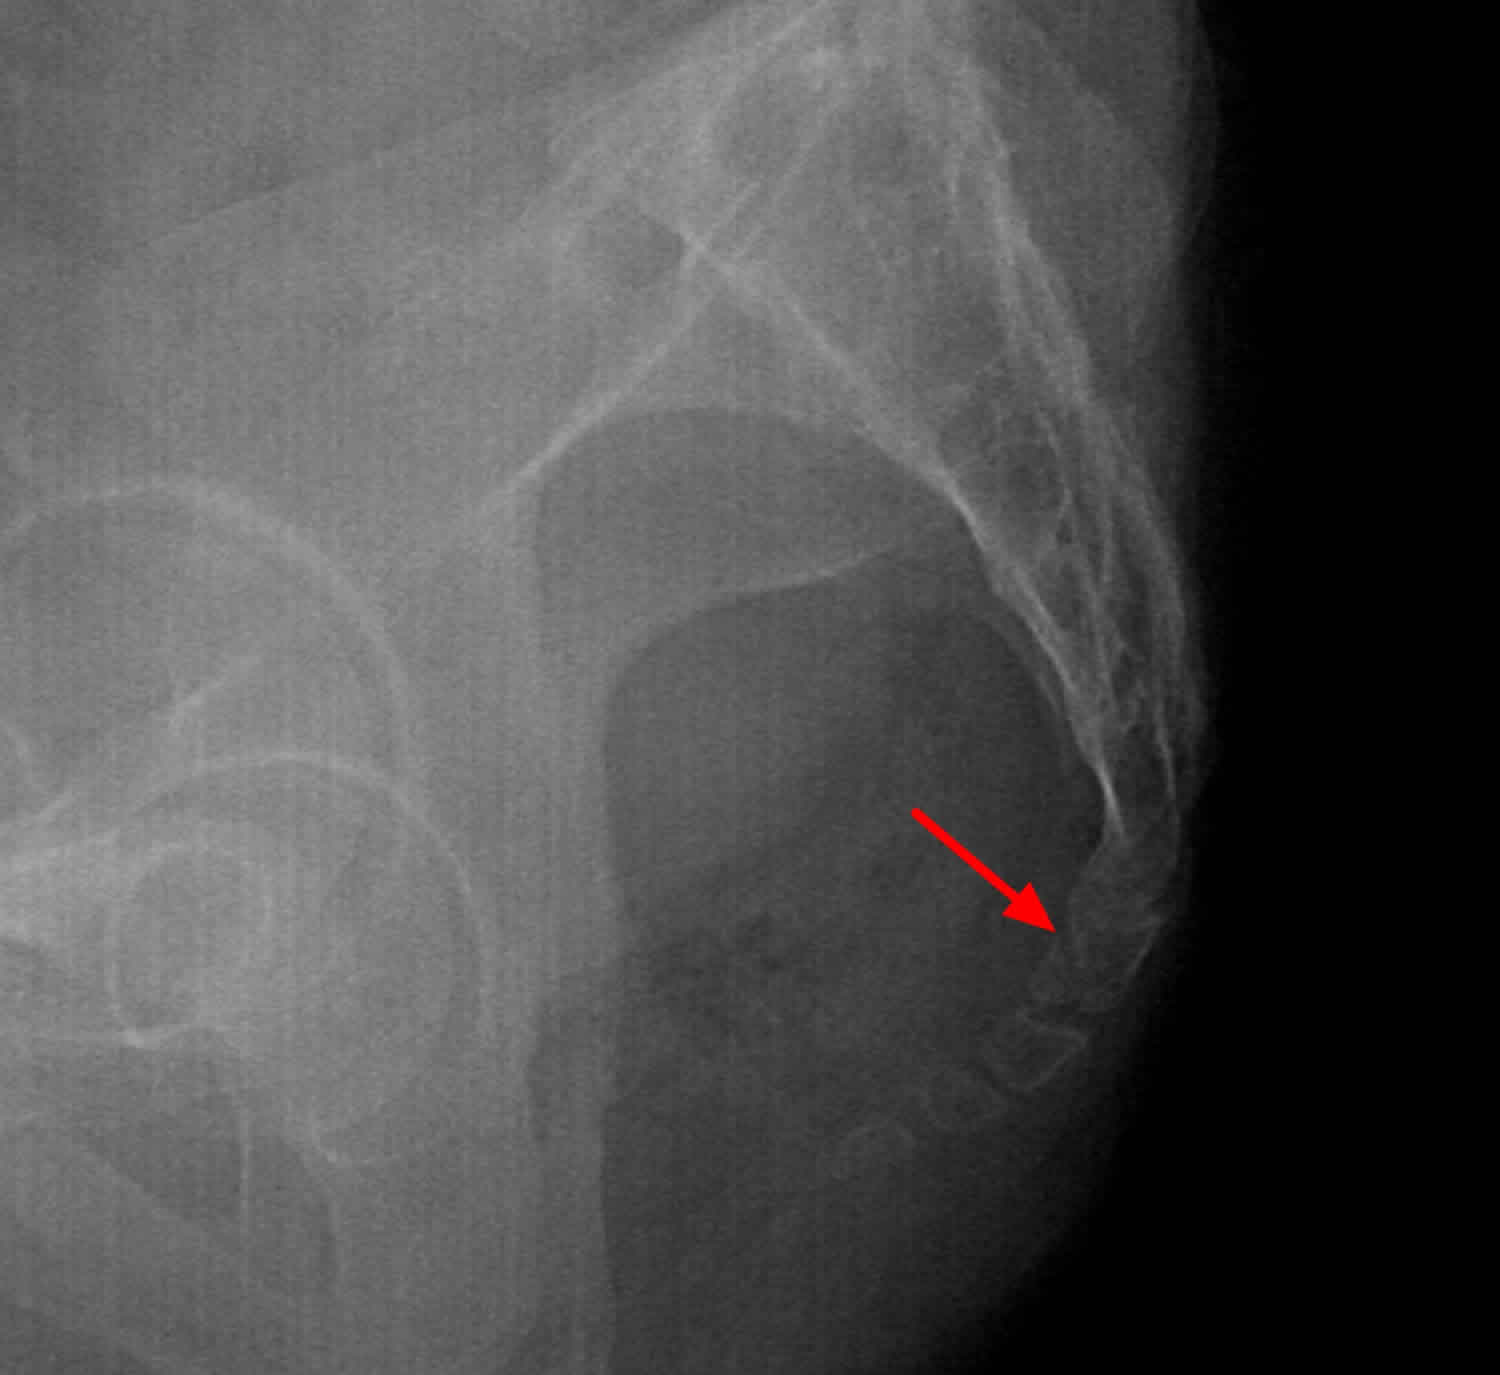

Рентгеновские снимки крестцово-копчикового отдела позвоночника